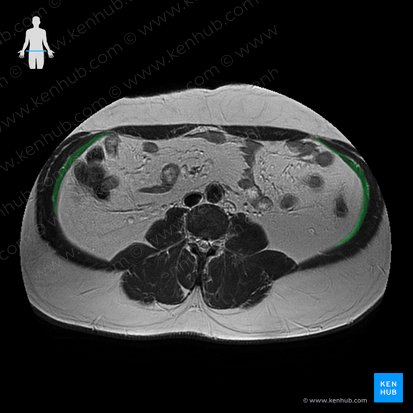

Musculus transversus abdominis

Der Musculus transversus abdominis (querer Bauchmuskel) ist der tiefste Muskel der vorderen Bauchwand. Er wird zu den seitlichen Bauchmuskeln gezählt. Manchmal wird er auch als Constrictor abdominis bezeichnet, da seine langen Muskelfasern zur Einschnürung der Taille führen.